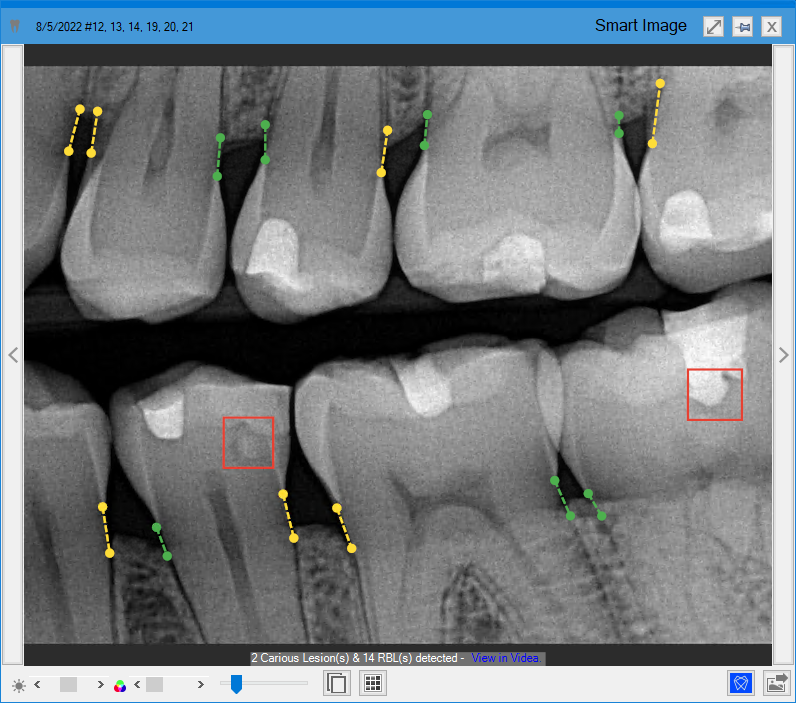

Dentrix Detect AI measures and analyzes the bone level from the cementoenamel junction to the alveolar bone in patients' bitewings and Periapical Radiographs (PAs). Measurements are in millimeters and the percentage of bone loss is annotated on the X-ray in green, yellow, orange, or red. These annotations make it easier for providers to visually communicate the key indicators of periodontal disease and to discuss potential treatment.

The Diagnostic Viewer appears, the image processes, any caries Dentrix Detect AI found are outlined in red, and RBL measurements appear in green, yellow, orange, or red.

3. To view the RBL measurements in millimeters, hover your mouse pointer over the desired RBL measurement indicator.